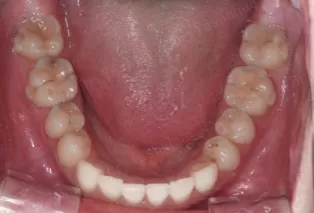

Intraoral photos after treatment